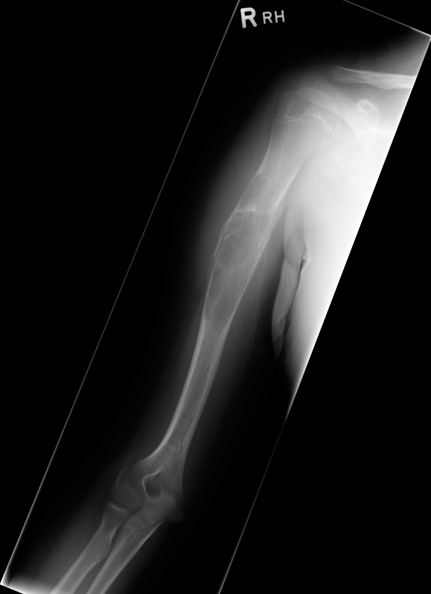

Learning Objectives: At the conclusion of the general orthopedic self-assessment exam physician assistants should be familiar with radiographic characteristics of benign and malignant bone tumors, be able to identify common benign bone tumors including enchondroma, unicameral bone cyst, nonossifying fibroma, osteoid osteoma, aneurismal bone cyst, giant cell tumor, and osteochondroma, be able to identify common malignant bone tumors including osteosarcoma, chondrosarcoma, and Ewing’s sarcoma, and be able to identify and understand treatment of pathological fractures from metastatic disease.